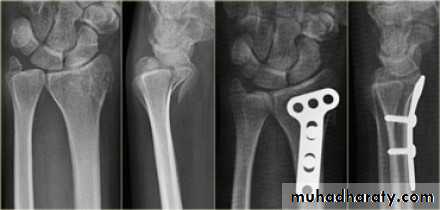

Fall on out stretched hand

xray

Management

Surgery